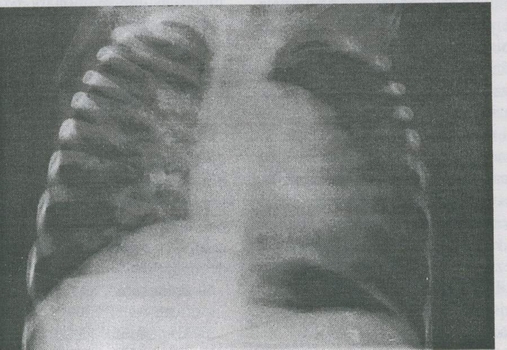

Fig. 9-4. Defect septal ventricular nerestrictiv cu hipertensiune pulmonara majora (organica, fixa) = complex Eisenmenger. Radiografia cardiopulmonara arata cardiomegalie, proieminenta accentuata (prin dilatare) a trunchiului arterei pulmonare, congestie vasculara pulmonara accentuata.

constant, factor de desaturare sistemica si cianoza. Zgomotul II puternic, HVD majora si exclusiva, dilatarea arterei pulmonare probata radiologie si echocardiografic, cresterea presiunii sistolice īn artera pulmonara sunt caracteristice sindromului. In timp, apare poliglobulie si cianoza se accentueaza. Evolutia este fatala īn cele din urma.

Situatii particulare. Complexul Eisenmenger apare īn cazul īn care nu s-a actionat terapeutic īntr-un DSV larg cu comunicare nerestrictiva si hipertensiune pulmonara majora de tip obstructiv si se ajunge la inversarea suntului. suntul dreapta-stānga devine